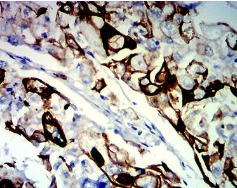

KRT13 Mouse Monoclonal antibody[7D7B3]

The protein encoded by this gene is a member of the keratin gene family. The keratins are intermediate filament proteins responsible for the structural integrity of epithelial cells and are subdivided into cytokeratins and hair keratins. Most of the type I cytokeratins consist of acidic proteins which are arranged in pairs of heterotypic keratin chains. This type I cytokeratin is paired with keratin 4 and expressed in the suprabasal layers of non-cornified stratified epithelia. Mutations in this gene and keratin 4 have been associated with the autosomal dominant disorder White Sponge Nevus. The type I cytokeratins are clustered in a region of chromosome 17q21.2. Alternative splicing of this gene results in multiple transcript variants; however, not all variants have been described.

IHC    1/200 - 1/1000